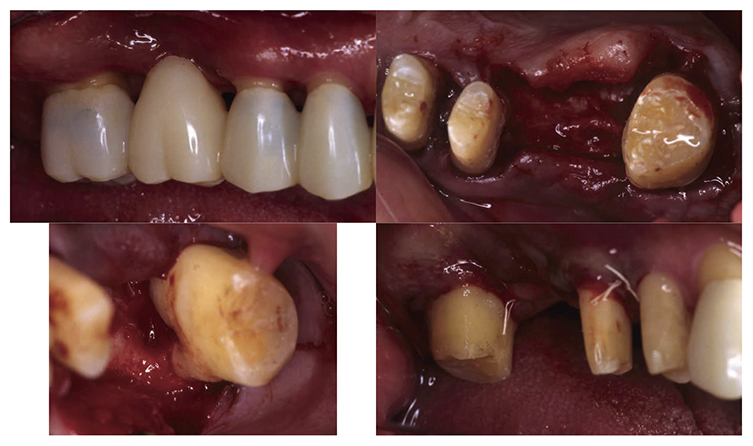

At the reevaluation examination after completion of basic periodontal treatment, deep periodontal pockets and grade 2 furcation involvement were observed. Therefore, in April 2010 (age 42), enamel matrix proteins were applied in a procedure for periodontal regeneration (Fig.4),and in June of the same year, gingival flap operation and distal wedge procedure were performed on 27 (Fig.5). For the remaining PD on the lingual side of 36 and 46, due to insufficient keratinized gingiva, the option was to stabilize the condition with SRP.

Fig 4

(Fig.4) Enamel matrix proteins were applied in a procedure for periodontal regeneration in the maxillary left molar (April 1, 2020)

Fig 5

(Fig.5) Gingival flap operation and distal wedge procedure were performed on the maxillary left second molar (June 2010)